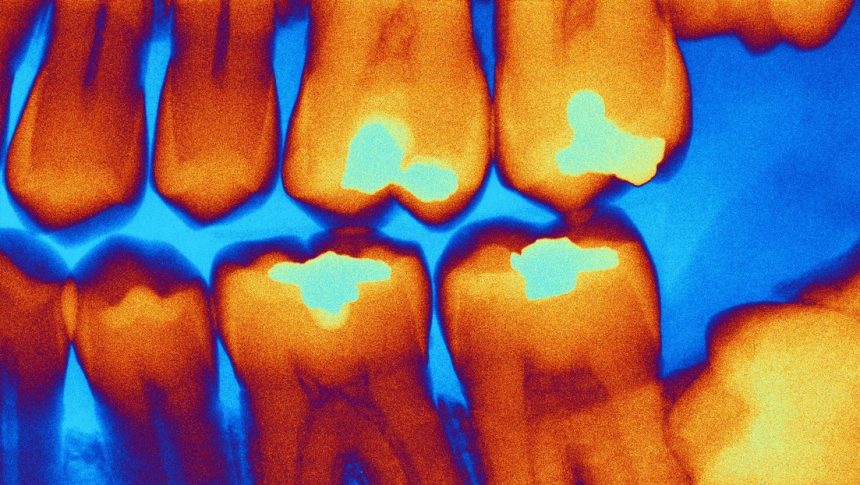

Investigadores de la Universidad Sechenov de Moscú han desarrollado un nuevo dispositivo capaz diagnosticar caries durante una cita dental en tiempo real, una tarea que suele resultar difícil incluso para especialistas experimentados.

Según explicó la institución a medios locales, distinguir la dentina infectada por caries, que debe retirarse, de la dentina dañada pero aún viable, que conviene conservar, es uno de los mayores retos en el tratamiento de las caries. Aunque existen tintes especiales que ayudan a identificar el tejido afectado, estos prolongan el procedimiento y requieren pasos adicionales.

El nuevo aparato evita estos inconvenientes gracias a un método no invasivo basado en una sonda óptica que se aplica a la superficie del diente. El dispositivo registra la fluorescencia del tejido y envía la información a un ordenador, donde un modelo de aprendizaje automático determina al instante el tipo de dentina.

“Este es un enfoque fundamentalmente nuevo para la toma de decisiones clínicas”, señaló Elena Nikonova, investigadora del Laboratorio de Biofotónica Clínica de la Universidad Sechenov. “Ayudamos al dentista a obtener datos objetivos directamente durante la preparación de la cavidad, lo que reduce el riesgo de eliminar tejido sano”, destacó.